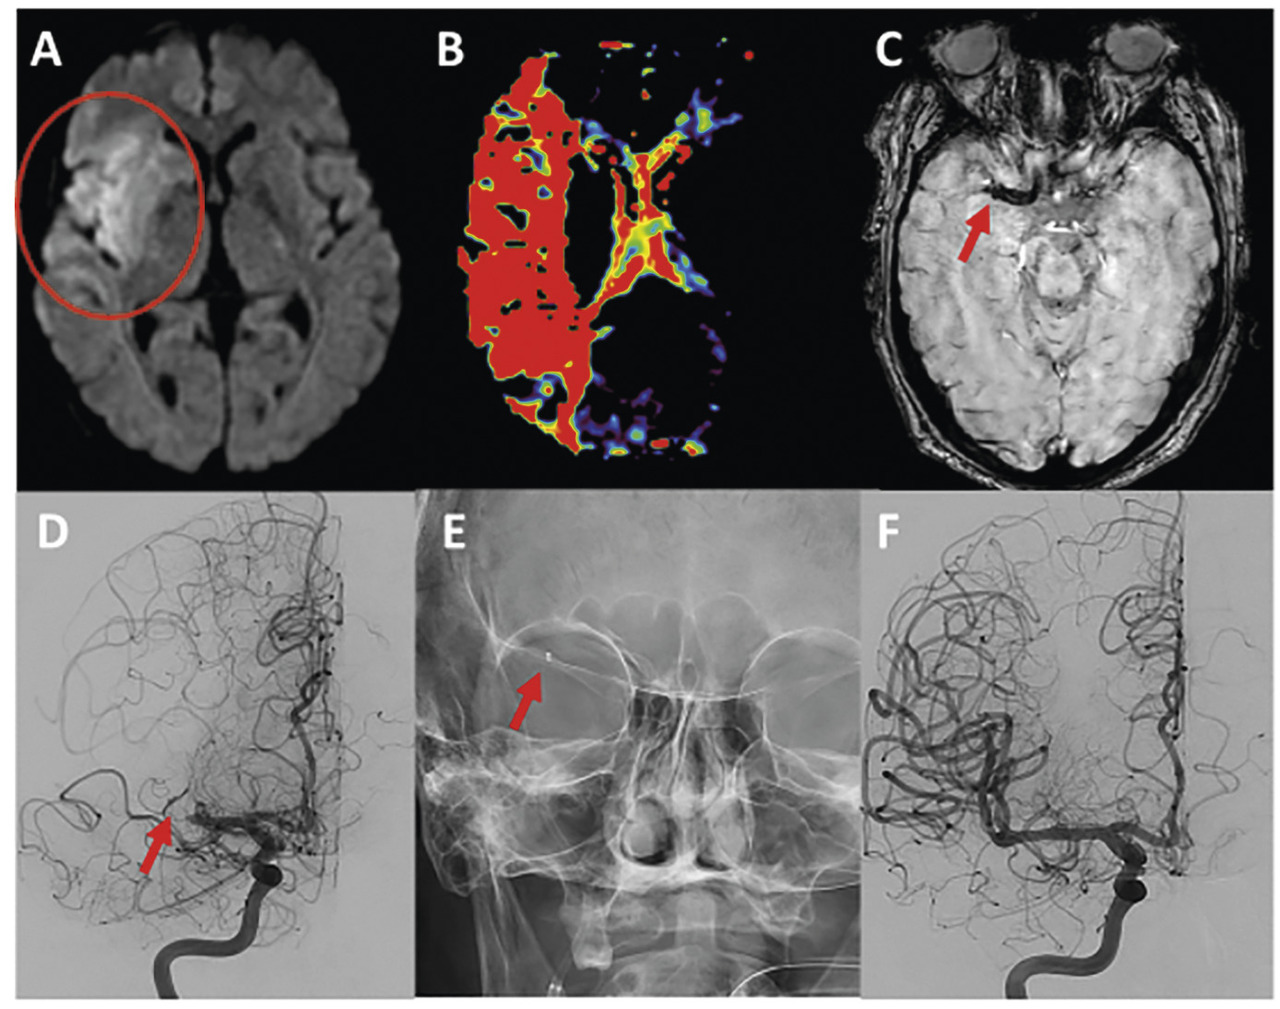

Après ponction de l’artère fémorale commune, un cathéter porteur de large calibre est monté jusque dans la carotide interne ou l’artère vertébrale, en amont de l’artère cérébrale occluse. Des clichés artériographiques, avec injection de produit de contraste iodé, confirment et précisent le niveau et le degré de l’occlusion. Un microcathéter est alors introduit à l’intérieur du cathéter porteur et navigué sur un microguide jusqu’au-delà de l’occlusion intracrânienne.

Actuellement, 2 techniques ont une efficacité équivalente : le stent retriever, stent auto-expansif non largable, déployé par le microcathéter en regard du niveau de l’occlusion. En ouvrant ses mailles, le stent capture le caillot. Autre technique : l’aspiration directe (figure ). Un cathéter spécifique connecté à une pompe dédiée est amené au contact du thrombus pour une aspiration de plusieurs minutes avant son retrait.

Actuellement, 2 techniques ont une efficacité équivalente : le stent retriever, stent auto-expansif non largable, déployé par le microcathéter en regard du niveau de l’occlusion. En ouvrant ses mailles, le stent capture le caillot. Autre technique : l’aspiration directe (